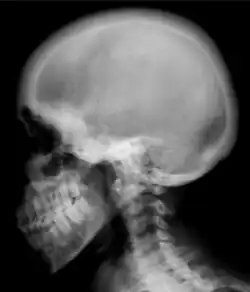

Ground glass density of the skull.[18] -